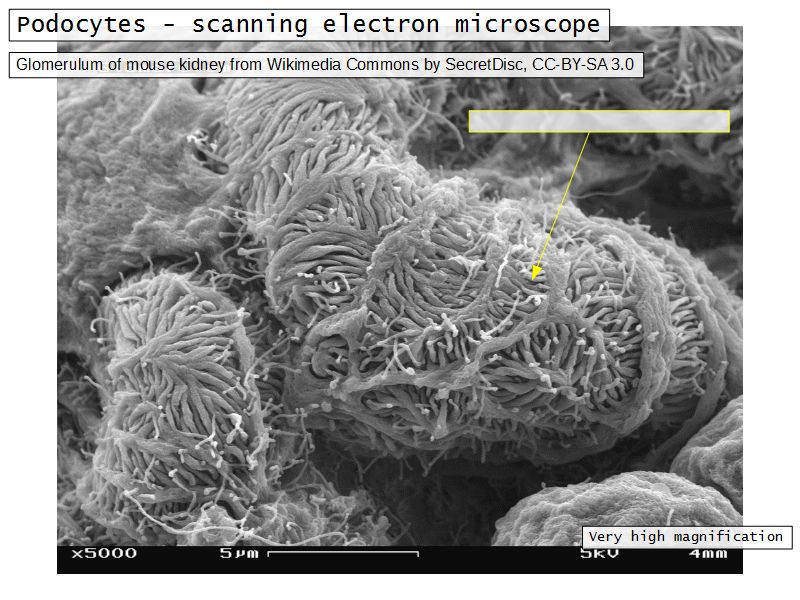

Epithelium layers

- Capillary endothelium

- Visceral layer of epithelium

- Podocytes

- Resting on glomerular basement membrane

- Capsular space

- Parietal layer of epithelium

- Simple squamous epithelium

Podocytes

- Visceral layer of epithelium

- Protrude into capsular space

- Attached to basement membrane

- Long cytoplasmic extensions

- Primary processes

- Secondary processes

- Podocyte feet

- Tightly spaced

- Filtration slits 20 - 30 nm wide